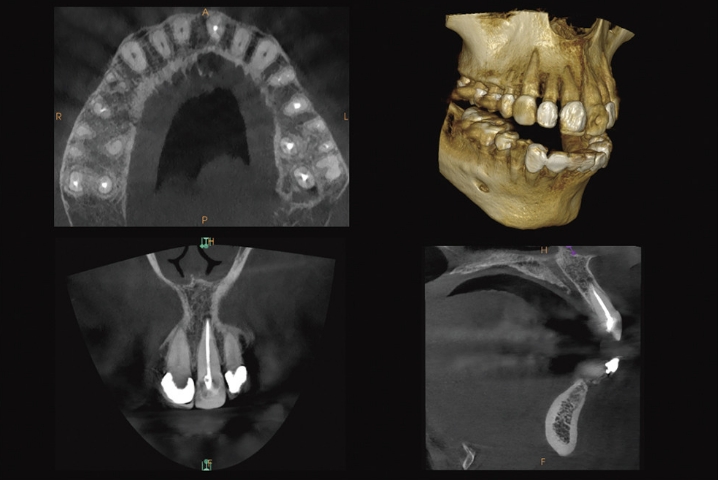

難治症例に対しては、低線量歯科用CTレントゲンを用いて原因の追及をする事も可能です。

レントゲンでは発見困難な病巣の広がりや根管形態を3Dで確認できます。

セファロ写真(横顔のレントゲン)や歯型を分析し、それぞれにあった治療プランをご提案致します。